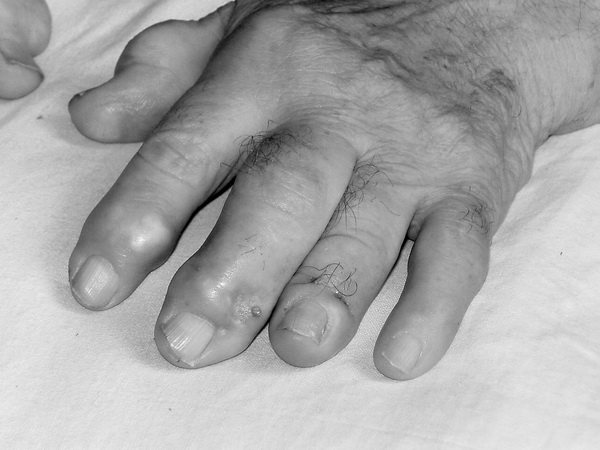

2. Сидят с опущенными ногами, откинув голову назад, при сердечной недостаточности (ортопноэ): уменьшается застой крови в легких, разгружается малый круг кровообращения, и, таким образом, уменьшается одышка (рис. 1).

Рис.1. Положение больного с хронической сердечной недостаточностью.